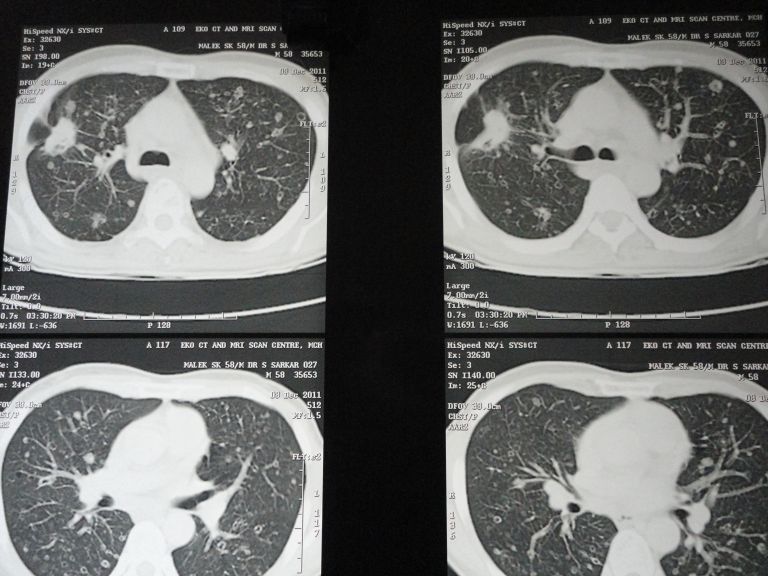

Adenocarcinoma and squamous cell carcinoma are the most frequently diagnosed histological subtype of bronchogenic carcinomas. Though metastatic lesions in lung are common in both the varieties, cavity formation has been documented only with squamous cell type. Here we are going to report a case of pulmonary adenocarcinoma with multiple nodular metastases in both lungs which show central necrosis mimicking cavities.